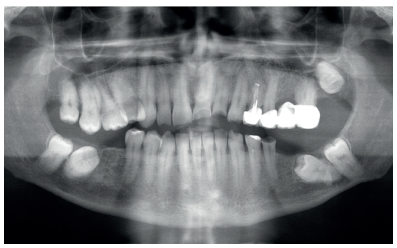

En una primera visita se realiza la historia clínica, serie de fotos intraorales y extraorales, así como una radiografía panorámica para planificar el caso conjuntamente entre el Máster de Prótesis Bucofacial y el Máster de Cirugía Bucal e Implantología. (Figura 2). Como consecuencia de las ausencias del primer y segundo molar inferior de ambos cuadrantes, el paciente presentaba desgastes generalizados en el resto de los dientes debido una sobrecarga e inestabilidad oclusal. Con todos los registros clínicos y radiográficos, se decidió conjuntamente entre Cirugía y Prótesis realizar una rehabilitación completa superior e inferior sobre dientes e implantes. Debido a las limitaciones económicas del paciente, se sugirió la posibilidad de emplear los segundos molares inferiores, que se encontraban retenidos, como material de injerto para la posterior colocación de implantes en esas áreas. Tanto el tercer como el cuarto cuadrante fueron tratados de la misma forma.